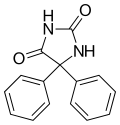

On appelle hydantoïnes les dérivés substitués de l'hydantoïne. Ces composés ont des propriétés relativement similaires à celles des imidazolidines, les dérivés saturés des imidazoles. Elles sont utilisées en pharmacie comme antiépileptiques. On peut notamment citer parmi les composés pharmaceutiques de type hydantoïne :

- la phénytoïne ;

Éthotoïne Phénytoïne

Phénytoïne Méphénytoïne